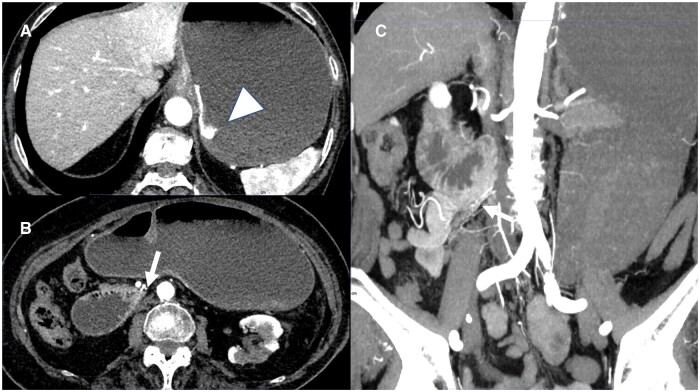

A 77-year-old woman underwent CT to evaluate haematemesis. The images showed that the third part of the duodenum flexed steeply on the right side of the aorta and ran caudally, without crossing anterior to the aorta. The duodenal-jejunal junction and jejunum were located on the patient's right side. Upper gastrointestinal endoscopy revealed a laceration at the gastric cardia, and a diagnosis of Mallory-Weiss syndrome was made. Repeat CT 7 days later revealed that the abnormal positioning of the intestinal tract had resolved spontaneously. Two months later, the patient experienced another episode of haematemesis, and CT revealed repeat deviation of the duodenal-jejunal junction and jejunum to her right side. Upper gastrointestinal endoscopy revealed another laceration at the gastric cardia, as in the previous study. On the basis of the initial CT findings showing the duodenal-jejunal junction in the right hemi-abdomen, intestinal malrotation was suspected. However, because the jejunum deviated repeatedly to the right side but resolved spontaneously, we diagnosed dysplasia of the ligament of Treitz. Laparotomy revealed a formed ligament of Treitz; however, fixation in the upper jejunum was incomplete. Additionally, CT revealed that the anterior pararenal space was loosely fixed and mobile. These factors may have caused the right-sided deviation of the small intestine. In this case, the third part of the duodenum likely flexed on the right side of the aorta, causing an obstruction that resulted in repeat vomiting episodes and Mallory-Weiss syndrome.

一位77岁的女性接受了CT检查以评估呕血情况。图像显示十二指肠第三段在主动脉右侧急剧弯曲并向尾侧延伸,未穿过主动脉前方。十二指肠-空肠交界及空肠位于患者右侧。上消化道内窥镜检查显示贲门处有撕裂伤,诊断为Mallory-Weiss综合征。7天后复查CT显示肠道定位异常自行消退。2个月后,患者再次出现呕血,CT显示十二指肠-空肠交界处和空肠再次向右侧偏移。上消化道内窥镜检查显示贲门处有另一个撕裂伤,与先前的研究相同。根据最初的CT表现显示十二指肠和空肠交界在右半腹部,怀疑肠旋转不良。然而,由于空肠反复向右偏但自行消退,我们诊断为Treitz韧带发育不良。剖腹探查发现形成的Treitz韧带;然而,上空肠的固定是不完整的。此外,CT显示肾旁前间隙松散固定并可移动。这些因素可能导致小肠向右偏移。本例中,十二指肠第三部分可能在主动脉右侧屈曲,造成阻塞,导致反复呕吐和Mallory-Weiss综合征。